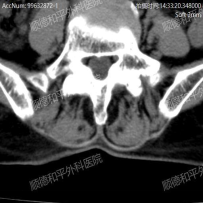

经过询问病史、详细查体及完善腰椎检查后,发现吴阿姨是因为腰椎间盘突出伴神经根的机械性卡压导致左下肢的放射性疼痛。

最终诊断为:“腰椎退行性变、腰椎左凸侧弯畸形、T12椎体压缩性改变、L5/S1椎间盘膨出伴真空变性、多节段椎管狭窄”等复杂腰椎病变,建议手术治疗。

手术过程中,决定采用后入L5/S1椎间盘摘除、L4/5椎间盘植骨融合内固定术治疗。在麻醉科、手术室通力配合下,不到一个小时手术顺利完成。